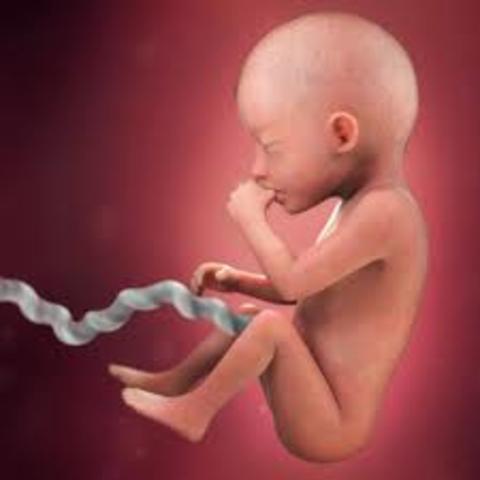

• development at 20 weeks

development at 20 weeks

baby weighs 10 ounces the baby starts sucking thumbs yawn and stretch